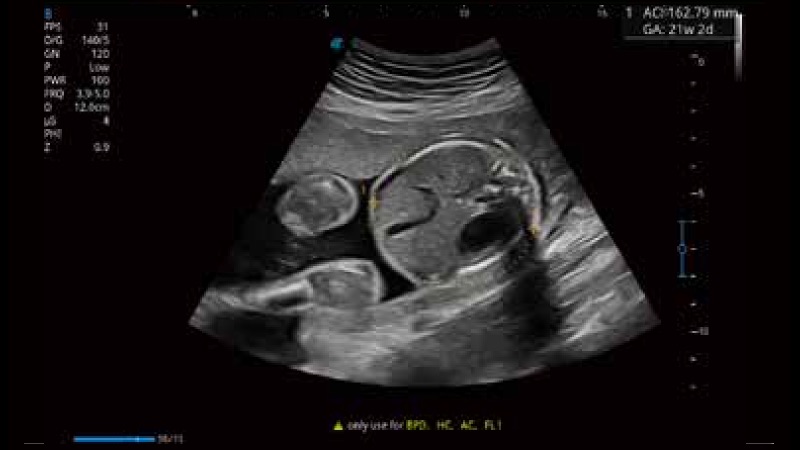

開立醫(yī)療通過不斷的技術(shù)創(chuàng)新,為大眾的生命健康提供持續(xù)關(guān)愛。P12 Plus采用全新一代超聲成像平臺,新平臺旨在將真實(shí)還原組織解剖結(jié)構(gòu)作為首要目標(biāo)。平臺采用全新集成化硬件模塊,搭載新一代芯片,系統(tǒng)性能得到大幅提升,為您的診斷提供了豐富的臨床信息。優(yōu)異的圖像表現(xiàn),豐富的探頭配置,全面的應(yīng)用功能,為您日常診斷提供了可靠的助手。

彩色多普勒超聲診斷系統(tǒng)